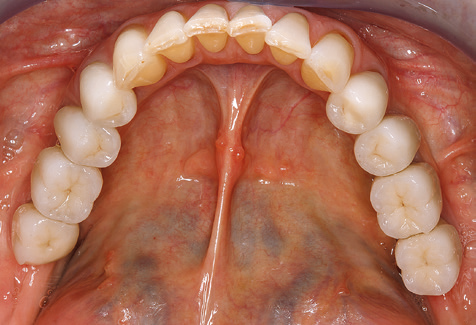

Fig. 9: The accessible implant and tooth surfaces are polished with polishing cups and suitable polishing compounds. – Fig. 10: Repeat instruction in the use of appropriate aids for oral hygiene at home should also form part of SPT. – Fig. 11a and b: Clinical situation 12 years after insertion of the prosthetic restoration. During this period, only a veneering ceramic fracture on tooth 47 and the requirement for endodontic treatment of tooth 12 were observed. All restorations are still functioning as intended.

Standardised and regular risk-adapted care in the scope of SPT is the key to treatment success for the clinical long-term success in periodontically compromised patients. This is particularly true for patients fitted with implants following successfully completed periodontal treatment (Fig. 11a and b).